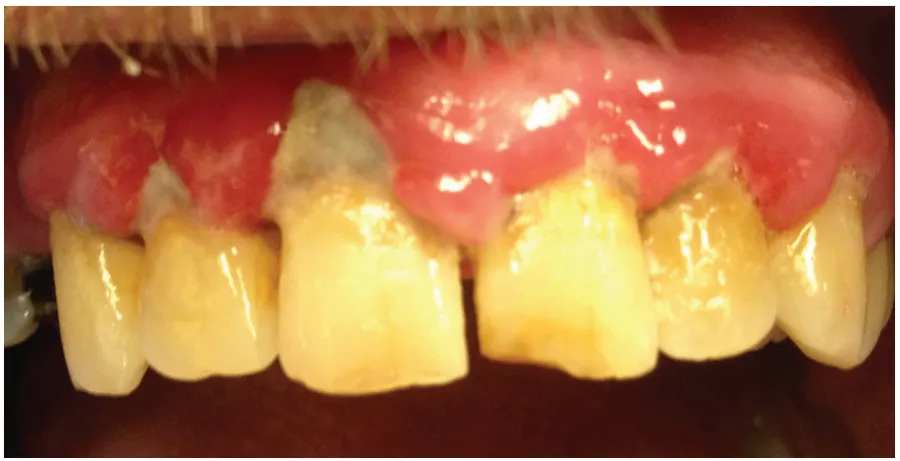

2- آتشی روی زخم لثهها: تحریک و سوختگی لثه

یکی دیگر از عوارض بلیچینگ دندان، تحریک و سوختگی لثهها است که میتواند باعث ناراحتی و التهاب در بافت نرم اطراف دندانها شود. مواد شیمیایی سفیدکننده در برخی موارد ممکن است با لثه تماس پیدا کنند و منجر به قرمزی، سوزش و حتی زخمهای کوچک در ناحیه لثه شوند. این حالت نه تنها دردناک است، بلکه ممکن است روند بهبودی و سفید شدن دندان را نیز تحت تأثیر قرار دهد.

راهحل: برای کاهش تحریک لثه، استفاده از محافظهای مخصوص بلیچینگ و شستوشوی ملایم با آب ولرم پس از درمان توصیه میشود؛ همچنین در صورت بروز سوختگی، مشورت با دندانپزشک جهت درمان سریع ضروری است.